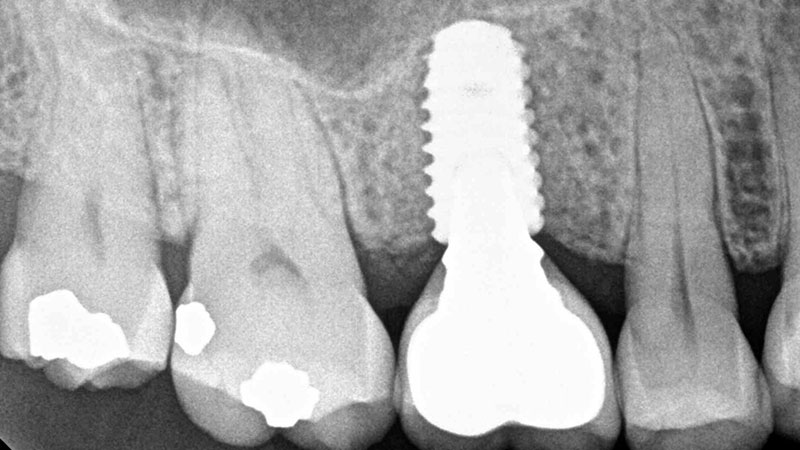

Cone Beam Computed Tomography (CBCT) in Endodontics: A Case Series

Clinical examination and radiographic imaging are the key steps in diagnosis and treatment planning in endodontics. Up until recently, intraoral, panoramic, and occlusal radiographs were the only imaging modalities available to dentists to rely on. These radiographs are two-dimensional (2D) images of three-dimensional (3D) structures with their inherent limitations such as image distortion and superimposition. … Read more